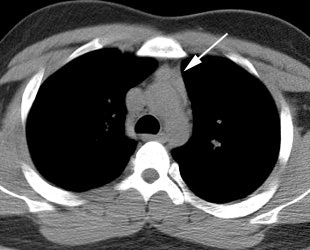

Thymic uptake on post therapy scan: The young male patient below received a 150 mCi ablation dose of I-131 for papillary thyroid cancer. On the post therapy scan, a triangular shaped area of tracer uptake was noted in the chest (black arrow). This was not seen on the pre-therapy diagnostic scan (not shown). CT imaging revealed normal thymus (white arrow). Radioiodine uptake in the thymus is thought to be related to tracer accumulation in Hassall bodies (Hassell corpusles) which are structurally similar to thyroid folliclesand sodium-iodide symporter expression [110]. Note the hepatic activity which is consistent with metabolism of radiolabeled thyroxine. Uptake in the neck is related to residual thyroid tissue. Normal naso/oropharyngeal activity is also seen. |